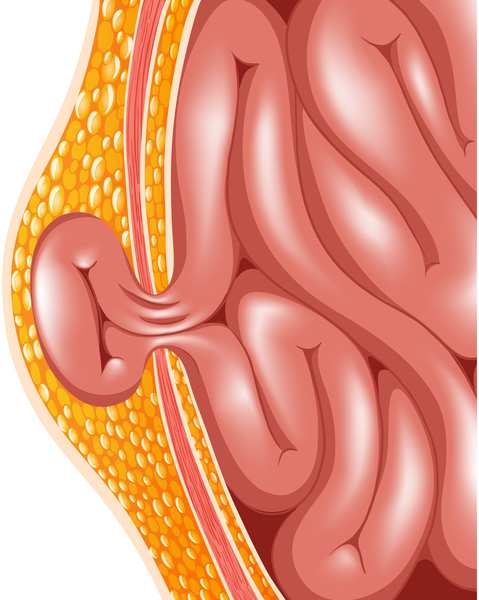

A hernia occurs when an internal organ pushes through a weak spot in the muscle, causing pain and swelling. At Dr Bharat Oza-Best General Laproscopy Surgeon PCMC in Punawale, hernia treatment is provided through advanced laparoscopic procedures.

Laparoscopic hernia surgery involves smaller incisions, which leads to less discomfort and a faster recovery compared to open surgery. This modern approach is highly effective for inguinal, umbilical, and incisional hernias, ensuring long-term relief and reduced risk of recurrence.